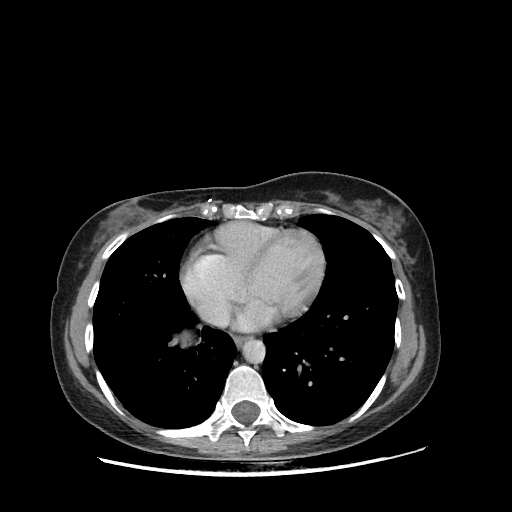

Generated VENOUS CT scan (A→B translation)

Full window (WL 1023.5, WW 4095 β†’ Low βˆ’1024, High +3071)

Actual HU range: [-1024.0, 892.4]